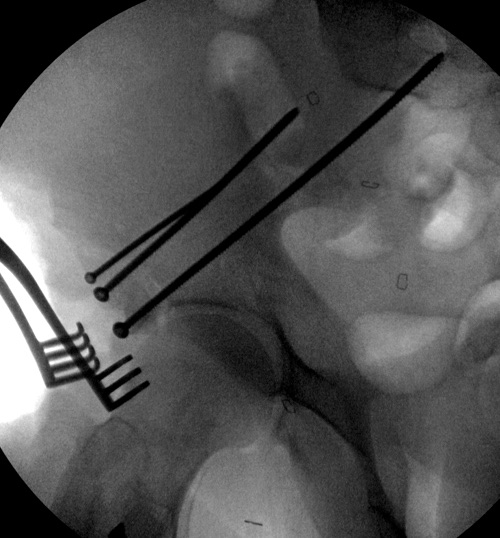

Появились новые проекции. Да, это высокий перелом передней колонны левой вертлужной впадины со смещением.

Перелом внутрисуставной, поэтому накостный остеосинтез предпочтительнее со всеми его плюсами. Кроме того, после операции можно тут же активизировать пациента, присаживать сразу, далее на костыли.

Не уверен, что с помощью АНФ можно точно сопоставить отломок передней колонны. При выламывании кости в этой области его и открыто сопоставить бывает сложно.

А есть другие проекции? Нет ли там поперечного перелома задней колонны?

Да, я понимаю, что предпочтительнее всего накостный синтез. Но если сравнивать АВФ с миниинвазивным, то ни тот ни другой не гарантируют 100%й репозиции. Перелом начинается с передней стенки впадины, идет вверх до крыла, а сзади спускаясь, останавливается едва достигнув задней колонны. Да, задняя колонна цела. Есть поперечные срезы КТ (сейчас показать не могу), где это четко видно. Перелом не завершенный. Учитывая этот факт, я и подумал о возможности АВФ. Простите мне мою упрямость)).